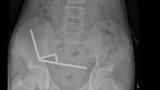

Yeni Zelanda’da 13 yaşındaki bir çocuk, neredeyse 200 yüksek güçlü mıknatıs yuttuktan sonra bağırsaklarının bir bölümünün cerrahi olarak alınması gerekti.

Tauranga Hastanesi’nde karın ağrısı şikayetiyle tedaviye alınan çocuk, yaklaşık bir hafta önce 100 kadar neodim mıknatıs yuttuğunu söyledi. Ancak yapılan ameliyatta midesinden çıkarılan mıknatıs sayısının iki katından fazla olduğu ortaya çıktı.

Röntgen görüntülerinde, çocuğun bağırsağında dört ayrı bölgede zincir halinde dizilmiş metal toplar görüldü. Ameliyatta bu zincirlerin ince bağırsak ve çekumda (kalın bağırsağın başlangıcı) birbirine yapışarak dokularda kan akışını engellediği ve “basınç nekrozu” denilen doku ölümüne yol açtığı tespit edildi.

Doktorlar, zarar gören bağırsak kısmını almak zorunda kaldı. Genç hasta sekiz gün sonra taburcu edildi.